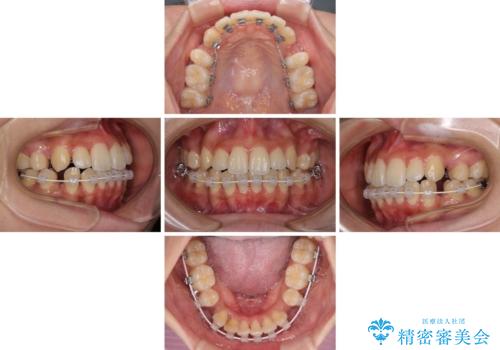

- ハーフリンガル

- 前歯のデコボコやクロスバイトと上顎の前突感による口の閉じにくさを気にして来院された患者様です。

目立たない装置を希望されたので、上顎が裏側装置のハーフリンガルを選択し、上下左右の小臼歯(計4歯)を抜歯して矯正治療を行うこととしました。